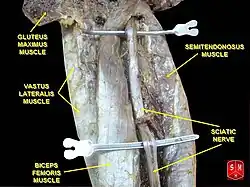

A ciática é geralmente causada pela compressão de uma ou mais de suas raízes lombossacrais, mas pode ocorrer devido à compressão do próprio nervo ciático.